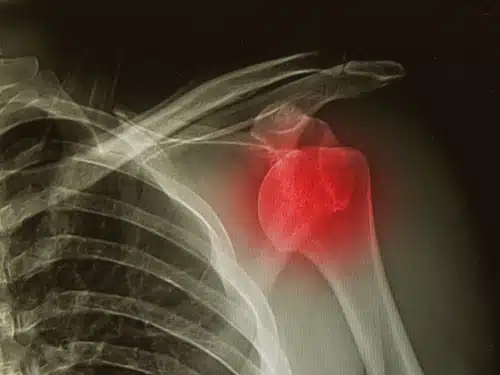

Studie zeigt: Schulter-OPs sind oft vermeidbar

Bei sogenannter „Schulterenge“ wird häufig operiert – zu Unrecht, wie eine Studie zeigt.